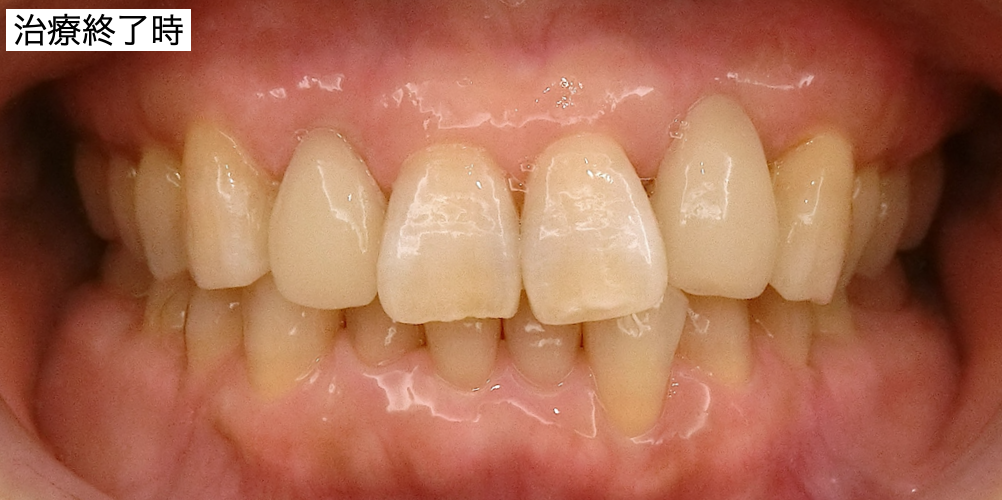

アンカースクリューによる右上の圧下も終えて、上部構造を装着しました。

上部構造装着後です。

患者さんはとても不安に感じておられたと思います。患者さんが勇気を出して手術を受けて下さった事に感謝しています。とても喜んで下さったので、良かったです。